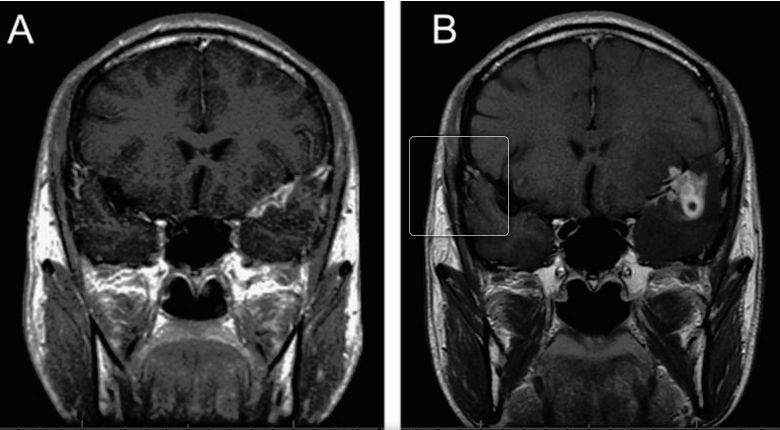

Studiul apărut în Nature Scientific Reports creează controverse în comunitatea ştiinţifică. Cercetătorii din domeniul biologiei moleculare, Diana Pisa, Luis Carrasco şi colegii lor au studiat 25 de cadavre, dintre care 14 aparţineau oamenilor bolnavi de Alzheimer. Ce au descoperit aceşti savanţi pare a fi incredibil. Toţi cei 14 care au fost bolnavi de Alzheimer au avut o infecţie fungică.

Este posibil, oare, ca această infecţie fungică să cauzeze simptomele demenţei? Diana Pisa şi colegii săi nu exclud această posibilitate. Astăzi există numeroase tratamente pentru infecţiile fungice cunoscute, iar cercetătorii afirmă că următorul pas este să fie testată eficacitatea acestor medicamente pe exponenţi care suferă de Alzheimer.